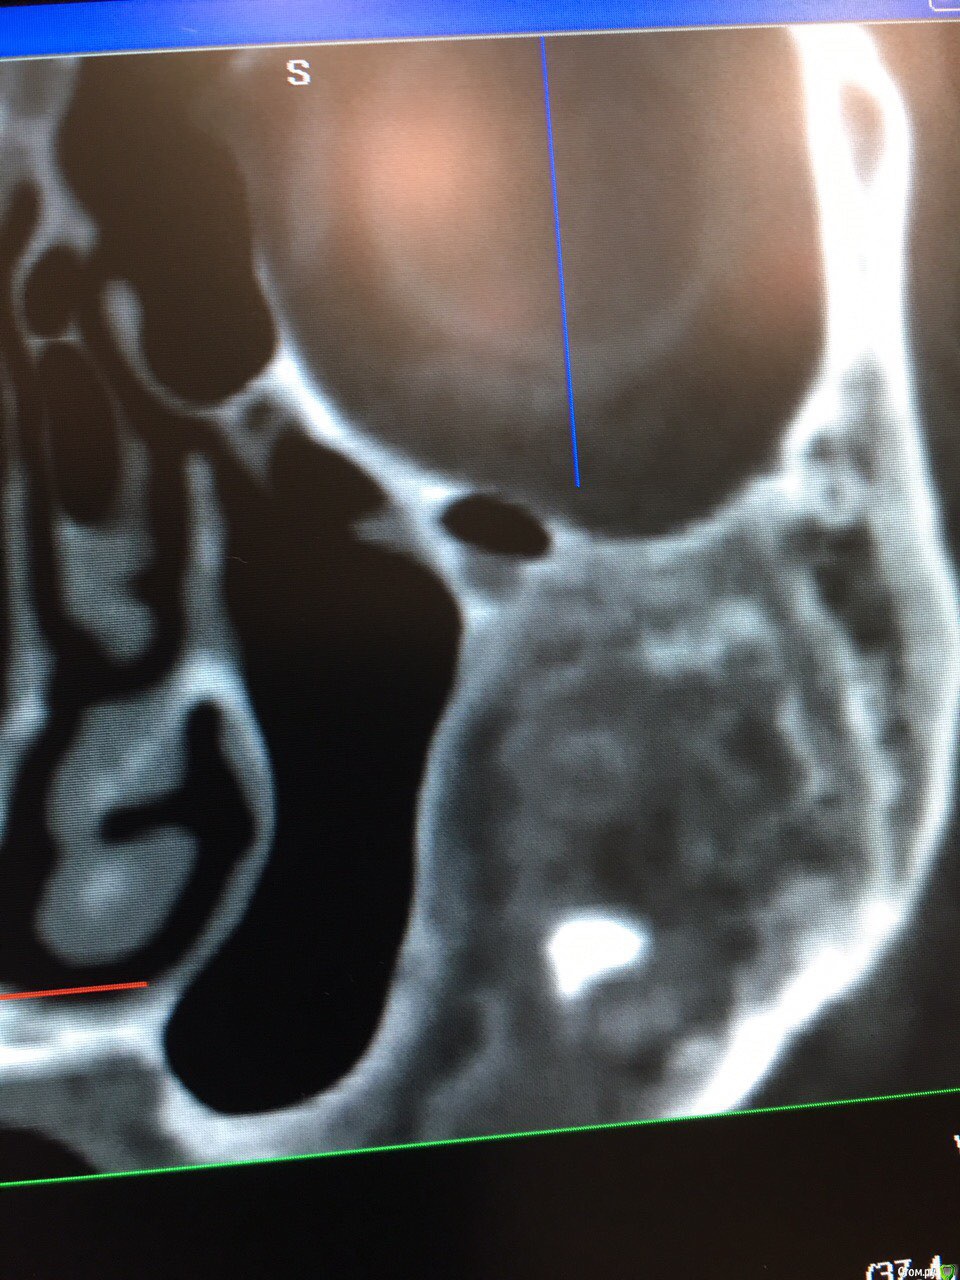

Kostoprav Опубликовано 17 августа, 2016 Поделиться Опубликовано 17 августа, 2016 знакомый рентгенолог прислал снимки, с его слов деформация лица почти отсутствует, пациента ничего не беспокоит.кто что думает? Ссылка на комментарий

Kostoprav Опубликовано 17 августа, 2016 Автор Поделиться Опубликовано 17 августа, 2016 вот еще Ссылка на комментарий